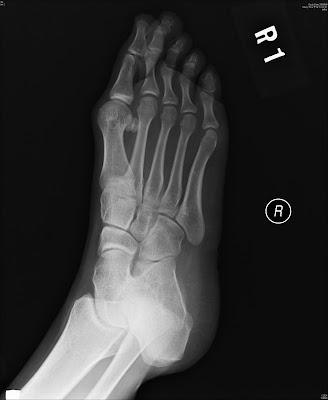

Hallux valgus

Right foot postop X-ray

Hallus valgus angle: pre-OP: 45 degree post-OP 15 degree

Intermetatarsal angle: pre-OP: 15 degree post-OP 11 degree